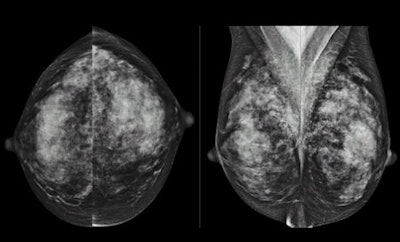

RSNA attendees heard much about breast tissue density as a cancer risk factor -- and what to do about it -- as well as clinical research that points to the efficacy of digital breast tomosynthesis (DBT) as a screening and diagnostic tool.

Images of woman with extremely dense breast tissue, which lowers the sensitivity of mammography. Courtesy of Dr. Wendie Berg, PhD.As for DBT, from posters to scientific sessions, researchers from around the world explored the technology's capabilities.

This research included a study that compared the performance of digital mammography alone to digital mammography plus tomosynthesis in detecting invasive lobular carcinoma, as well as another presentation that addressed the question of whether DBT can influence final BI-RADS assessment categories. Dr. Per Skaane from the University of Oslo presented research that showed that 2D images generated synthetically by a DBT device are clinically comparable to those acquired at conventional mammography -- cutting down on the radiation dose women receive.